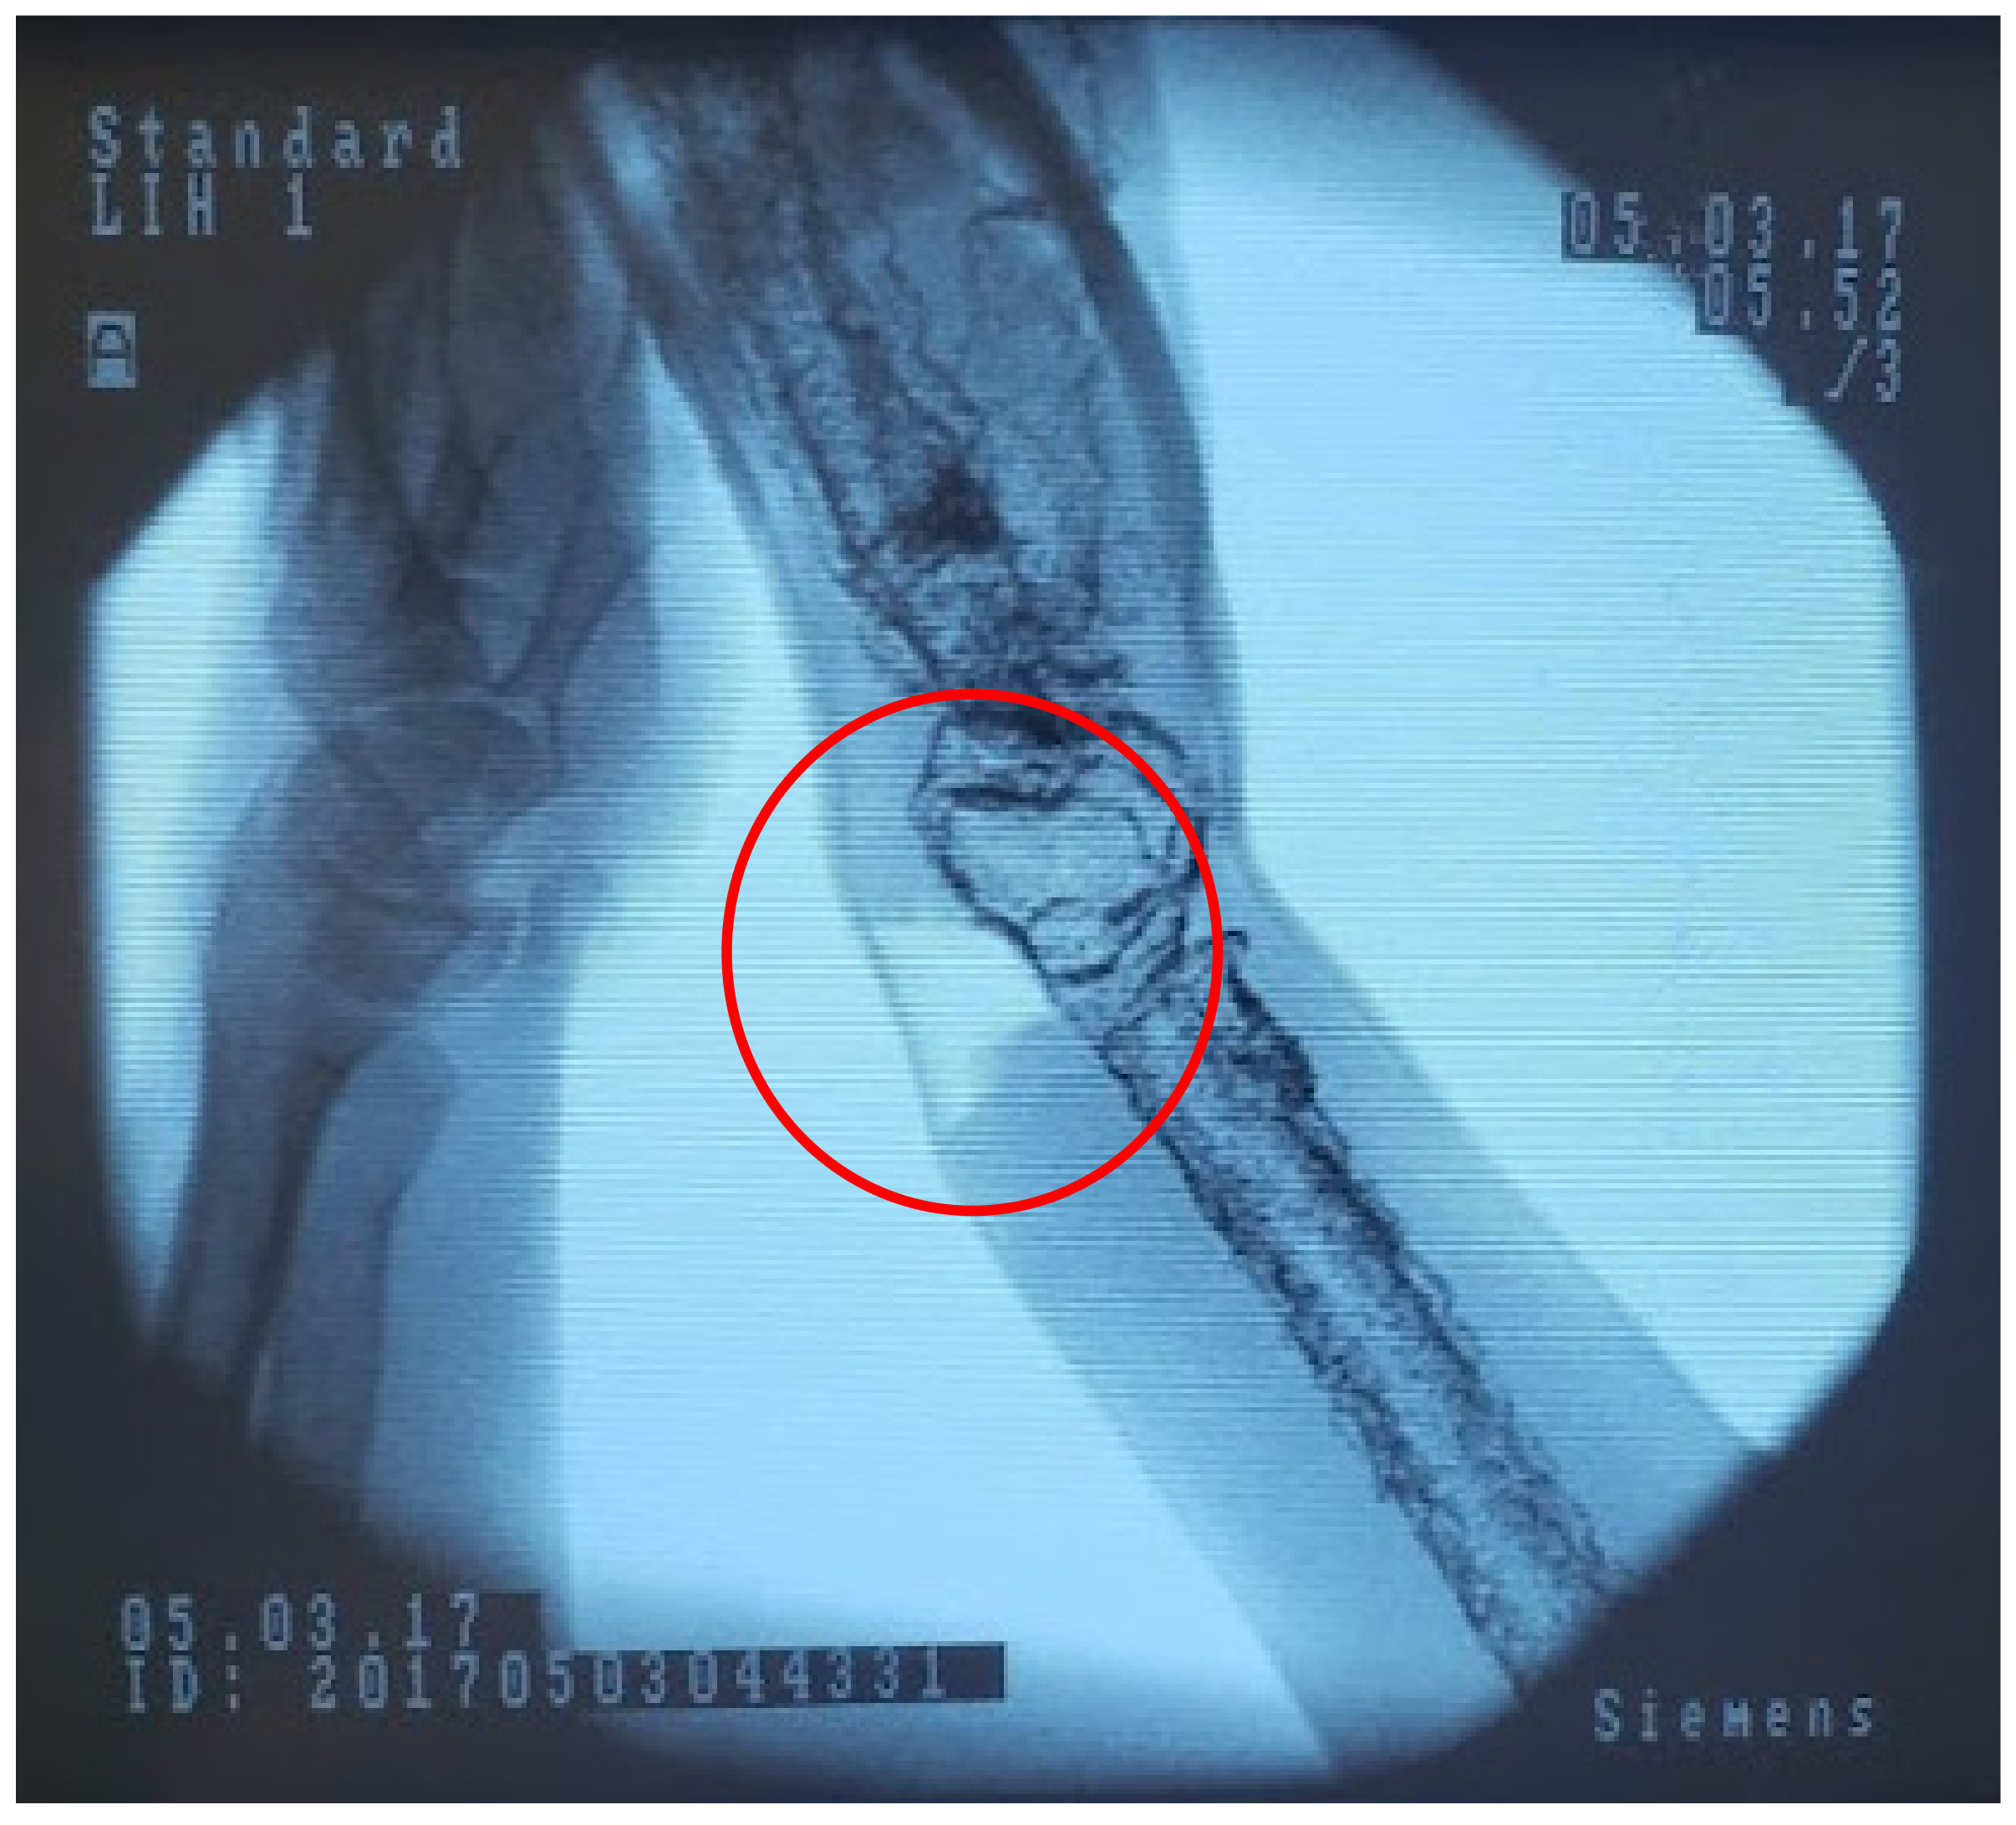

2.4. Medical Imaging